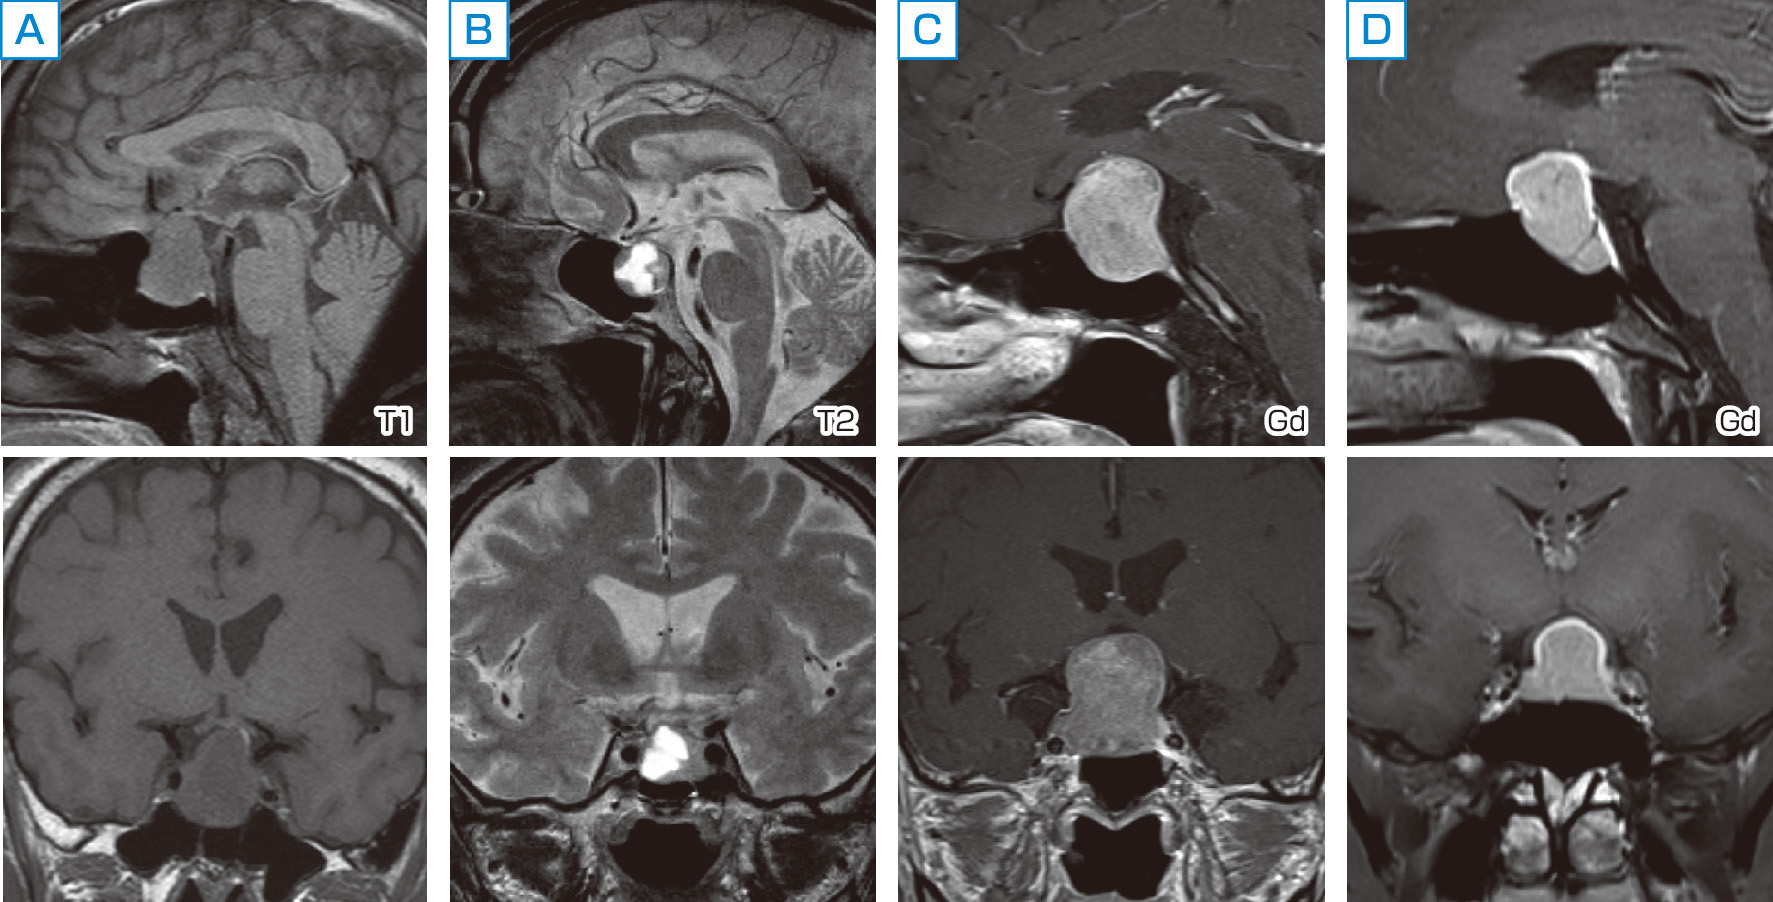

難治性甲状腺がんに対する標的アルファ線核医学治療 (Targeted, クッシング病(Cushing's disease) – 内分泌疾患 - 神戸きしだ,

クッシング病(Cushing's disease) – 内分泌疾患 - 神戸きしだ, 腎盂・尿管・膀胱癌 第2版(腫瘍病理鑑別診断アトラス) 宮居 弘輔,